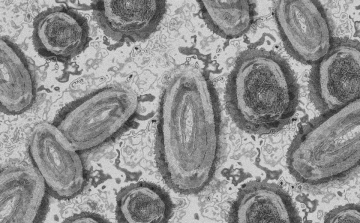

Még több hónapon át folytatódik a majomhimlő elleni oltási kampány Franciaországban

Franciaországban még több hónapon át folytatódik a majomhimlő elleni oltási kampány 2022-ben és várhatóan 2023 elején is, miután az általános megelőzés következtében most először csökkeni kezdtek a mutatók

2022. Augusztus 26. 16:04, péntek | Belföld

Tovább nőtt a majomhimlő-fertőzöttek száma Magyarországon

Újabb két embernél igazolt majomhimlő-fertőzést a Nemzeti Népegészségügyi Központ (NNK) a 33. héten - augusztus 15-től 21-ig -, ezzel 64-re nőtt a magyarországi esetek száma.

2022. Augusztus 25. 11:02, csütörtök | Külföld

Egy 3 év alatti gyermek fertőződött meg majomhimlővel Belgiumban

Belgiumban egy 3 év alatti gyermek fertőződött meg majomhimlővel - számolt be róla szerdán a Sudinfo hírportál.

2022. Augusztus 19. 16:02, péntek | Külföld

Meghaladta a 13 ezret a majomhimlő-fertőzöttek száma az Egyesült Államokban

Meghaladta a 13 ezret a majomhimlő-fertőzöttek száma az Egyesült Államokban, a legtöbb esetet Kaliforniában és New York államban regisztrálták.

2022. Augusztus 16. 17:01, kedd | Belföld

Megérkezett Magyarországra is a majomhimlő elleni védőoltás

Megérkezett Magyarországra is a majomhimlő elleni védőoltás: Magyarország 2560 adag vakcinát kap, amely 1280 ember oltására elegendő - közölte a Nemzeti Népegészségügyi Központ (NNK) kedden az MTI-vel.

2022. Augusztus 10. 07:00, szerda | Külföld

Megfertőződött a majomhimlővel egy gyerek Németországban

Megfertőződött majomhimlővel egy négyéves kislány Németországban - jelentették kedden német hírportálok az országos közegészségügyi intézet (RKI) adatai alapján.

2022. Augusztus 09. 07:00, kedd | Külföld

Elkezdődött a majomhimlő oltási kampánya Olaszországban

A fertőző betegségekre szakosodott Spallanzani római kórházban kezdődött el a majomhimlő elleni oltás hétfőn, miután az egészségügyi minisztérium adatai szerint 545 esetet azonosítottak.

2022. Augusztus 05. 06:00, péntek | Belföld

Tovább nőtt a majomhimlő-fertőzöttek száma Magyarországon

Újabb kilenc, 23-50 éves férfinél igazolták a majomhimlő-fertőzést Magyarországon, ezzel 42-re nőtt a fertőzöttek száma - közölte a Nemzeti Népegészségügyi Központ (NNK) csütörtökön az MTI-vel.

2022. Július 22. 07:00, péntek | Helyi

Újabb három majomhimlős esetet igazoltak Magyarországon

Újabb három majomhimlős esetet igazoltak Magyarországon, ezzel 33-ra nőtt az igazolt fertőzöttek száma - közölte a Nemzeti Népegészségügyi Központ (NNK) csütörtökön az MTI-vel.

2022. Július 15. 11:54, péntek | Belföld

Tovább nőtt a majomhimlő magyar fertőzöttjeinek száma

Újabb hat embernél diagnosztizálták a majomhimlő vírusát, így harmincra emelkedett az igazolt fertőzöttek száma Magyarországon - közölte a Nemzeti Népegészségügyi Központ (NNK) pénteken az MTI-vel.

2022. Július 09. 05:00, szombat | Belföld

Emelkedett az igazolt majomhimlő-fertőzöttek száma Magyarországon

Újabb öt embernél mutatták ki a majomhimlő-fertőzést Magyarországon az elmúlt héten, ezzel 24-re emelkedett az országban diagnosztizált betegek száma - közölte a Nemzeti Népegészségügyi Központ (NNK) pénteken az MTI-vel.

2022. Június 30. 09:52, csütörtök | Belföld

Újabb hét magyarnál igazolták a majomhimlőt

Újabb hét embernél igazolták a majomhimlőfertőzést a Nemzeti Népegészségügyi Központ (NNK) veszélyes kórokozókkal foglalkozó laboratóriumában; ezzel 19-re nőtt az igazolt majomhimlő fertőzöttek száma Magyarországon

2022. Június 29. 07:00, szerda | Külföld

Elkezdte a majomhimlő elleni oltóanyag vizsgálatát az EMA

Az Európai Gyógyszerügynökség (EMA) megkezdte a dániai székhelyű Bavarian Nordic biotechnológiai vállalat Imvanex nevű, himlő elleni oltóanyagának folyamatos felülvizsgálatát annak érdekében,